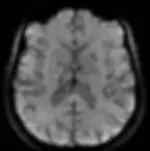

At Pacific West, our 3T MRI captures finer details that lower-strength MRIs may miss, allowing for earlier detection of abnormalities, clearer brain and joint imaging, and more precise diagnoses. When it comes to your health, precision matters—experience the unmatched advantages of 3T MRI technology.

SPECIFIC ADVANTAGES OF 3T IN NEURO

Clear visibility of brainstem structures (white matter tracts and deep cerebella nuclei

Determine Brain tissue viability following a stroke or TIA

A better picture of tumor environment from Venography

Clearer visualization of smaller vessels in Circle of Willis.

Higher resolution DTI and FiberTrack capabilities with the Ultra-high

Gradient System to prove TBI (Traumatic Brain Injury)

Higher resolution Susceptibility Weighted Imaging for more sensitive detection of brain microbleeds.